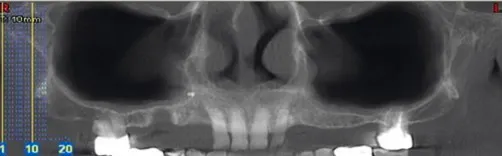

• Les différents clichés : possibilités et limites, avantages et inconvénients

• Diagnostic : du quotidien à l’exceptionnel